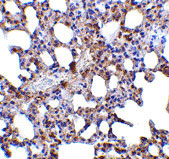

Immunohistochemistry of Blimp-1 in mouse lung tissue with Blimp-1 antibody at 5 μg/mL. |